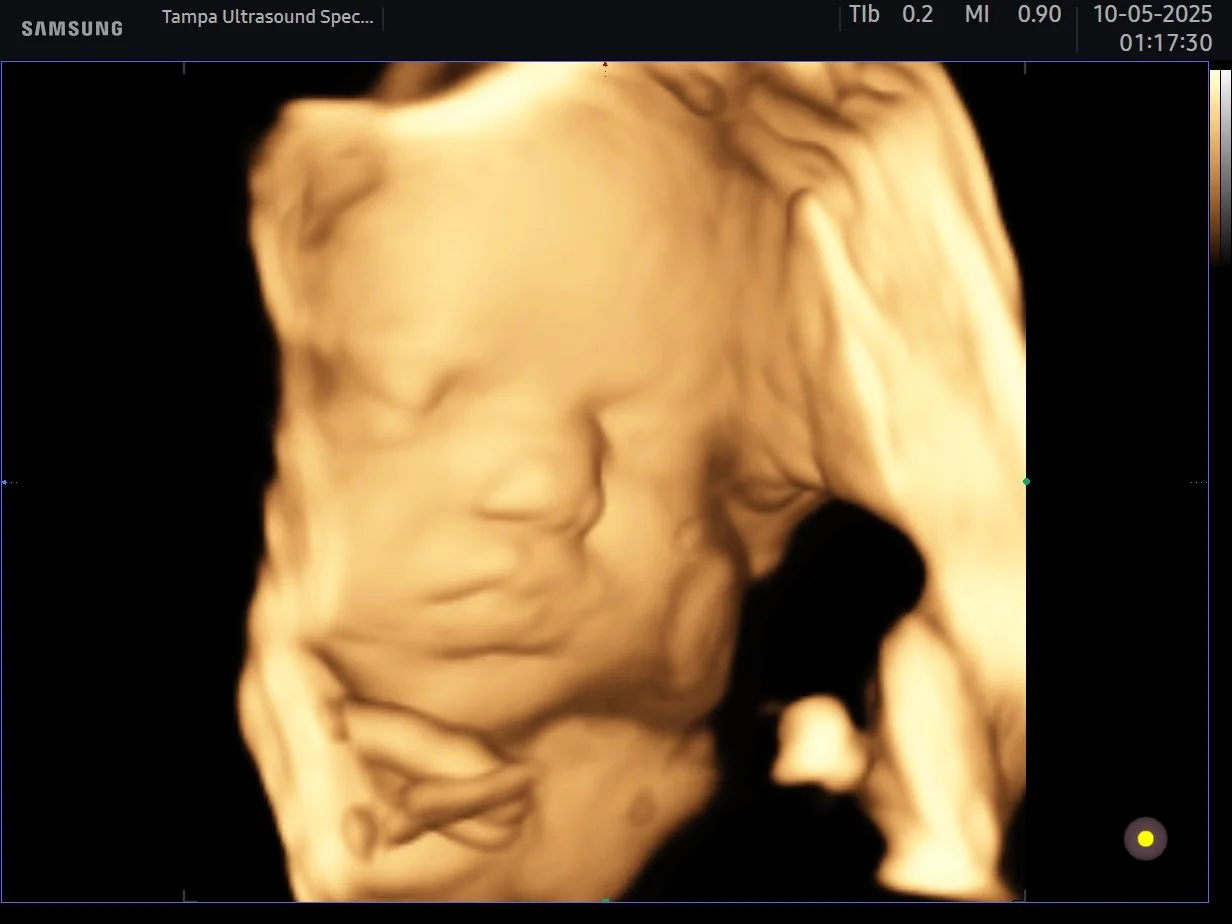

HD baby ultrasound tampa

3d4dHD tampa ultrasound